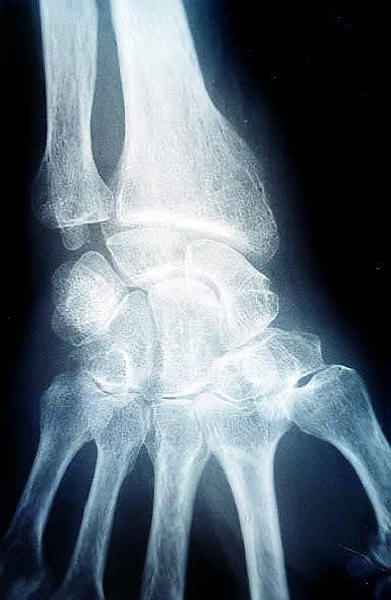

Carpo normal

ACT Alteraciones degenerativas en muñeca.